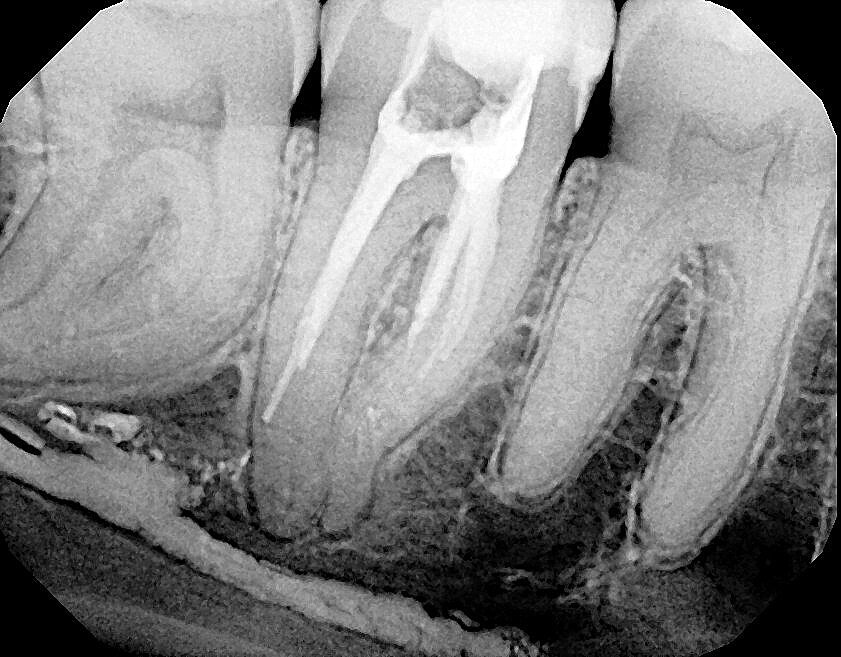

Fig. 17a: Case assisted with CBCT to determine anatomy pre-operatively. Note the multiple cross sections moving apically and the correlation to the 2-D view. Note also the conservative taper in relation to the root width. (Courtesy of Dr. Brett Gilbert)

Fig. 17b: Case assisted with CBCT to determine anatomy pre-operatively. Note the multiple cross sections moving apically and the correlation to the 2-D view. Note also the conservative taper in relation to the root width. (Courtesy of Dr. Brett Gilbert)

Fig. 17c: Case assisted with CBCT to determine anatomy pre-operatively. Note the multiple cross sections moving apically and the correlation to the 2-D view. Note also the conservative taper in relation to the root width. (Courtesy of Dr. Brett Gilbert)

Fig. 17d: Case assisted with CBCT to determine anatomy pre-operatively. Note the multiple cross sections moving apically and the correlation to the 2-D view. Note also the conservative taper in relation to the root width. (Courtesy of Dr. Brett Gilbert)

Fig. 17e: Case assisted with CBCT to determine anatomy pre-operatively. Note the multiple cross sections moving apically and the correlation to the 2-D view. Note also the conservative taper in relation to the root width. (Courtesy of Dr. Brett Gilbert)

Fig. 17f: Case assisted with CBCT to determine anatomy pre-operatively. Note the multiple cross sections moving apically and the correlation to the 2-D view. Note also the conservative taper in relation to the root width. (Courtesy of Dr. Brett Gilbert)

Managing complex anatomy is much simpler if the clinician has a pre-operative road map. The CBCT provides the roadmap and the surgical microscope the lens (literally) through which to visualize the result. Aside from a relaxed patient who is profoundly numb, being able to visualize anatomy by taking a pre-operative (and possibly intra-operative) CBCT and using a surgical microscope during treatment have no substitutes. They are the current “Gold Standard” in that 3-D imaging shows the clinician the true reality of a clinical situation as opposed to the suggestion gained from a 2-D radiograph. Proper interpretation of imaging prior to and/or during endodontic treatment goes a long way in taking the “guesswork” out of identifying canal location and other anatomical complexities as the procedure unfolds. In a 2014 study by El Fayad and Johnson, it was determined that when having a pre-operative CBCT as compared to 2-D radiographs alone, the treatment plan was modified 62 percent of the time. This is a huge game changer to think that the information learned from 3-D imaging changed the plan of treatment over six times out of 10 (Fig. 4).[2]